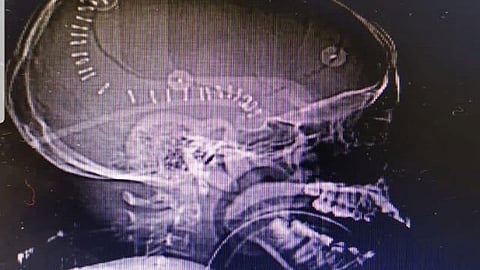

وتبيَّن بعد إجراء الفحوصات والأشعة اللازمة وجود نزيف سطحي مع ضغط على جذع الدماغ، مع بوادر الوفاة الدماغية. وعلى إثر ذلك تم تجهيز المريض في قسم الطوارئ إلى غرفة العمليات خلال ١٥ دقيقة وأجريت العملية للمريض.

ولفت هوساوي إلى أنه تمَّت إزالة النزيف عن طريق المايكروسكوب الجراحي، والمحافظة على أنسجة الدماغ بتقنية التبريد الدماغي خلال العملية التي استغرقت ساعتين، وتمت مرافقة المريض في العناية المركزة لمدة ٢٤ ساعة، وبعد إجراء العملية بثلاثة أيام خرج من المستشفى وهو بصحة جيدة.